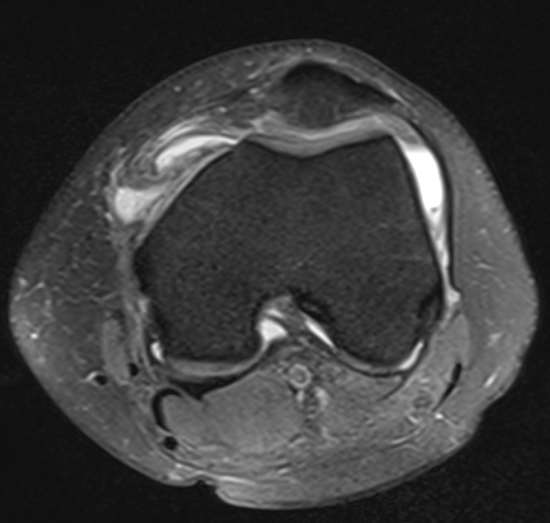

MRI

Articular Cartilage Damage

MPFL integrity

OCD

Loose Bodies